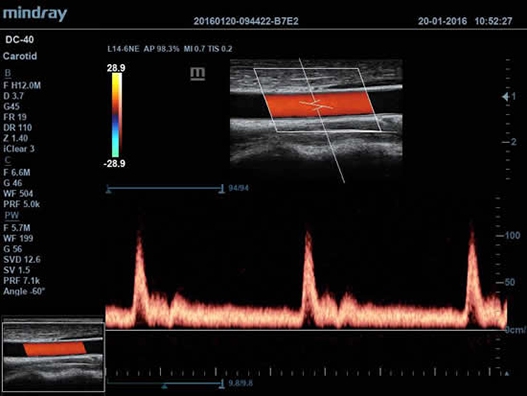

Mindray DC-40 - передовая УЗ-станция с выдающимися возможностями в области медицинской диагностики. Компания Mindray разработала это устройство с учетом высоких требований врачей к качеству изображения и быстродействию. DC-40 обеспечивает высокое качество изображения и точность диагностики, что является необходимым в повседневной практике врачей. Технологии, применяемые в этом устройстве, позволяют получать четкое и детализированное изображение.

Технологии iBeam, iClear и iScape, применяемые в DC-40, позволяют получать объемные изображения высокого качества без помех и зернистости в зоне сигнала. Панорамная визуализация с расширенным обзором анатомических структур решает проблемы сложных диагнозов, которые ранее создавали значительные трудности в ультразвуковой диагностике.

• Импульсно-волновой доплер (PW), включая режим доплеровского сканирования с высокой частотой повторения импульсов (HPRF);

• Цветной доплер (Color Doppler);

• Auto IMT Package – измерения и анализ толщины комплекса интимамедии (КИМ) сонной артерии;

• Мультичастотный линейный датчик Mindray L14-6

• Высокочастотный линейный датчик 38 мм Mindray l14-6NE